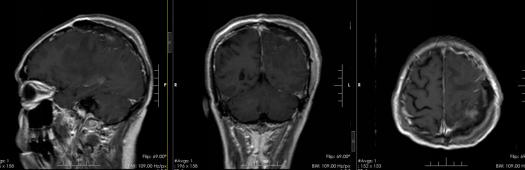

▲术后复查头颅MR

最终,神经外六科团队为陈大爷切除一个大小约为44mm×49mm×42mm的肿瘤,瘤子足有鸡蛋大。术后病理诊断为脑膜瘤,WHO I级。